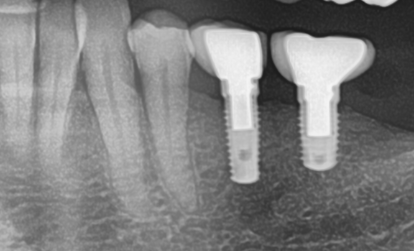

What are your thoughts about splinting two implant crowns at the end of the ridge (18+19)

is it advisable to splint them or just restore them separately.

I attached a screenshot. The two crowns were splinted originally but after screw loosening (many years ago) the were cut intraorally.

• Thanks for sending the x-ray. It seems like these implants have sufficient bony housing to withstand forces placed on them without having to splint them. I would leave them unsplinted. If the screw loosening happens again, you should consider using a brand new screw and perhaps reducing some of the occlusal contact on the tooth in question. Screw loosening can be a pain in the ass. It can take time to find the cause of it.